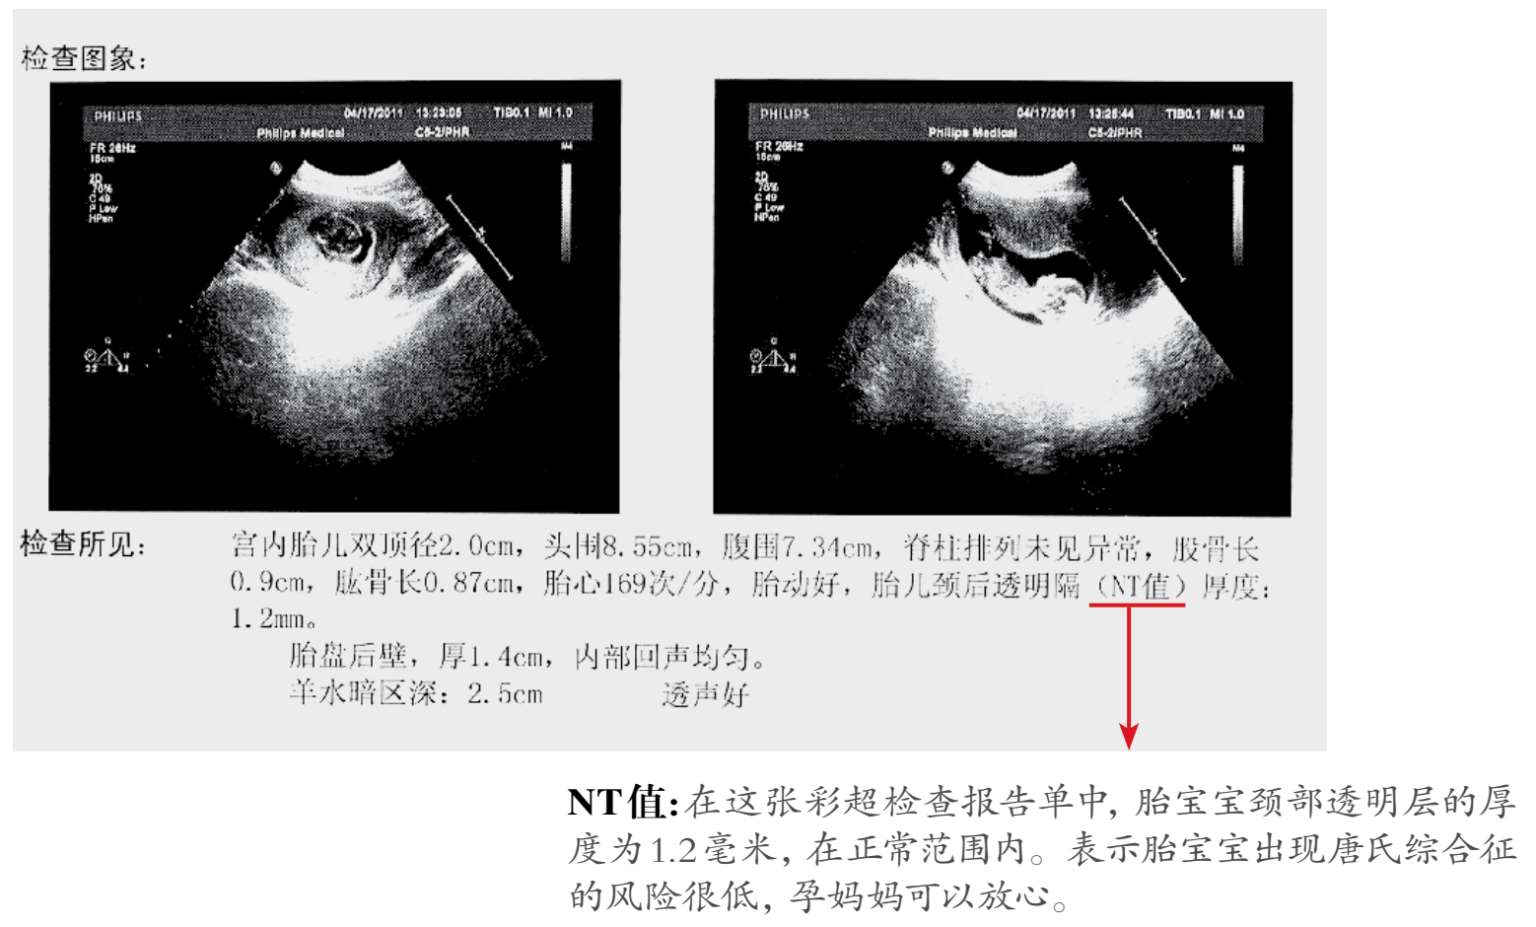

2.NT早期排畸检查

NT检查是什么

NT(Nuchal Translucency)是胎儿颈部透明层厚度的缩写。胎儿颈部透明层厚度与唐氏综合征缺陷正相关,所以这项检查被认为是筛查唐氏儿有效的早期指标。为了更精确地计算胎儿出现异常的可能性,NT检测会将一些至关重要的信息,比如孕妇的年龄,也一并考虑进去,最终给出胎儿患有唐氏综合征的风险概率。

孕11~14周检查最佳

NT检查最好在孕11~14周做,比孕中期唐氏综合征筛查时间更早,NT检查配合抽血化验,唐氏综合征的检出率能达到85%以上。在孕11~14周,98%~100%的胎宝宝可以检测出NT厚度,而过了孕14周,胎儿皮下的积水可能会被正在发育的淋巴系统吸收,降低到11%,导致检查结果不准确。

检查方法:B超

NT检查主要通过B超来进行测定,最终测量值小于3毫米为正常,超过3毫米就要考虑做进一步检查,如绒毛活检或羊膜腔穿刺等。NT检查配合抽血化验,唐氏综合征的检出率能达到85%以上。

检查结果为高危风险怎么办

即使检查结果呈现高风险,绝大多数孕妇也会生下健康的宝宝。NT检查的一个好处就是它的检查时间比较早,一旦检查出问题,还可以做绒毛活检,并提早知道结果。一定要直接咨询医生的意见,等到孕16周后做羊膜腔穿刺,抽羊水做产前诊断。 oese/Zme5mpKYZLEVrp03IwAyJlWAWE/kHYNAY6eYWLIOW3N73om5eXw0cqhTnQm